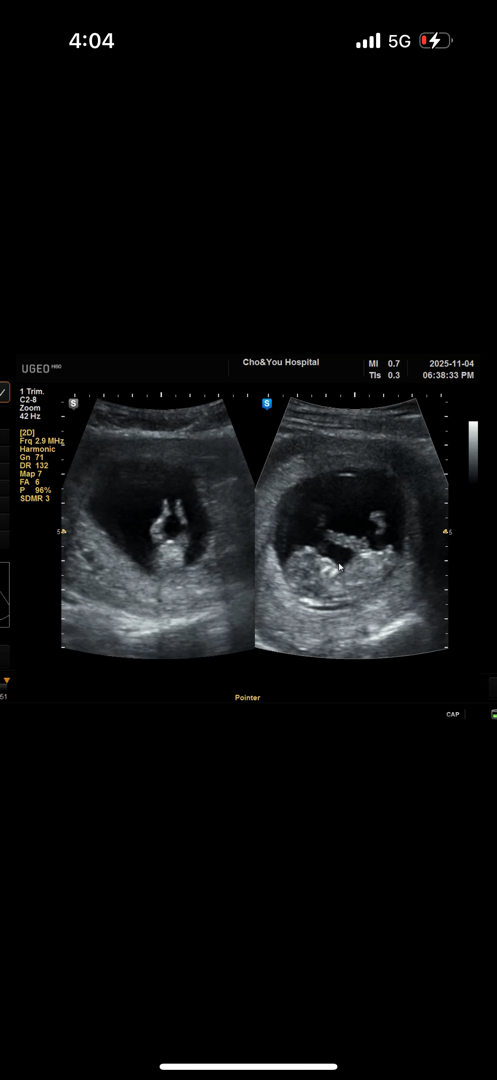

11주인데 성별 알수있을까요 ??

성별이 너무궁금해서 못참고 11주임에도 불구하고 여쭤봅니다!!><><

첫사진 자세가 너무 요가슨생님 같아요ㅋㅋㅋㅋㅋ 작으니 너무 😍 귀엽네요ㅎ